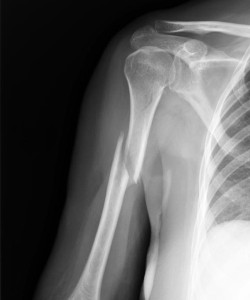

Диагностика

Для уточнения диагноза проводится рентгенография в двух проекциях. Иногда нужны дополнительные исследования. Например, при переломах диафиза плечевой кости очень важно исследовать целостность сосудисто-нервного пучка.

При переломе мыщелка плечевой кости с помощью рентгенограммы необходимо определить степень смещения, как и в случае с другими травмами. Если под костным фрагментом апоневроз разорван не до конца, это говорит о смещении только по ширине. Если же произошел полный разрыв апоневроза, происходит полное разобщение сломанных поверхностей. Такое смещение часто сопровождается интерпозицией. При эпифизеолизе дистального эпифиза трудно читать рентгенограмму у детей, если произошло небольшое смещение. В этом случае лучше сравнивать снимки поврежденной и здоровой руки. Независимо от того, в какой части произошел перелом плеча, в головке, диафизе, верхней трети или другой области, важно оказать первую помощь.